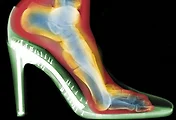

| 하이힐을 포기할 수 없는 여성들을 위한 Tip (0) | 2015.06.22 |